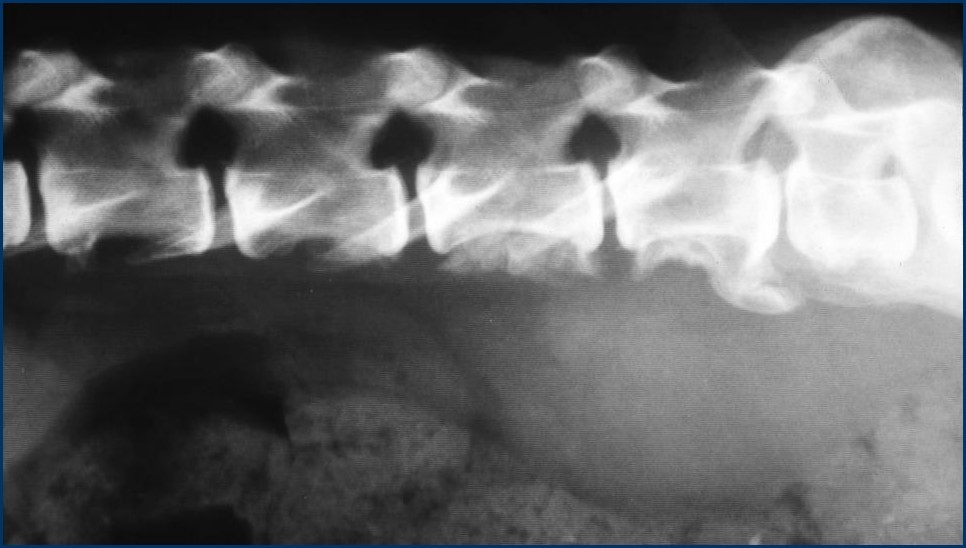

What can be seen here?

New bone on the ventral aspect of caudal vertebrae

Spondylosis

Between end plates – more irregular aggressive new bone

If you get this on caudal vert – pathognomic of neoplasia mets

Marked ST opacity ventralll – LN (infection, or neoplasia)